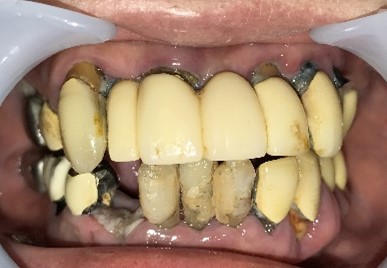

男性Iさん 50代(マグネット式入れ歯)

主訴

グラグラしている歯がある。歯並びをきれいにし、しっかり噛めるようになりたい。

治療内容

歯周病が進行し深刻な状態でした。保存することができない歯が上4本、下3本ありましたので、抜歯し、残った歯上4本、下7本の歯周病治療を徹底的にし、それらの歯を活用し上下マグネット式総入れ歯を入れました。

所感

治療前は、歯周病が進行し、重度に動揺している歯が4本あり、満足に食事ができない状況でした。マグネット式総入れ歯を装着後は、「なんでも思い通り噛むことができるだけでなく、歯並びもきれいになり、とても幸せです。」と、とても喜んでくださいました。

Before

赤丸は抜歯しました。上4本、下3本

After

【義歯を装着したところ】